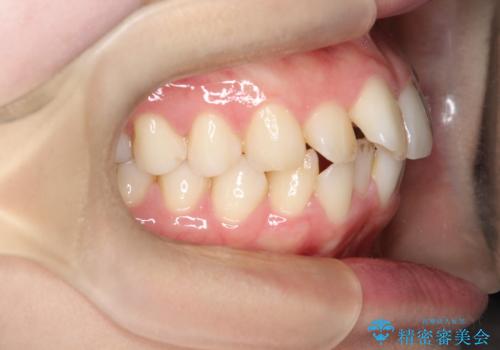

- 「歯のでこぼこと捻じれを治したい」を主訴に来院された患者様です。矯正検査の結果、上顎前歯がかなり唇側傾斜という結果になったので上下左右4番を抜歯をしワイヤー矯正で治療を行いました。

抜歯矯正でしたが順調に治療が進み2年で矯正治療を終えることが出来ました。歯のでこぼこや捻じれが治り、口元も下がって患者さんも大変満足されていました。